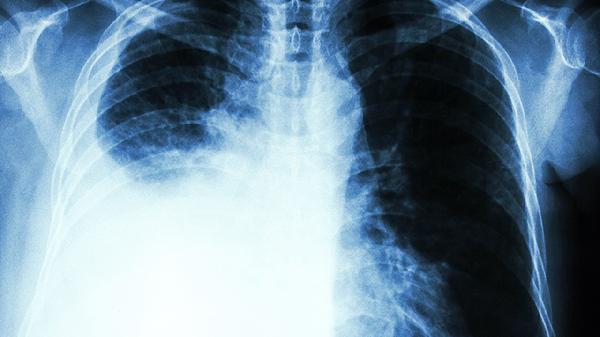

3、”拍胸片正常就沒事”

早期肺癌在胸片上可能只是個小斑點。低劑量螺旋CT能發現0.5cm的結節,檢出率是胸片的6倍。